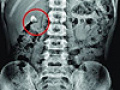

優卡丹被曝損害兒童腎臟 宋丹丹致歉